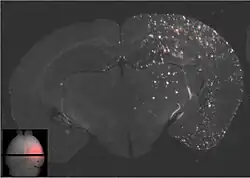

In den 1990er Jahren wurde in Versuchen mit Nanopartikeln, die aus biokompatiblen Polymeren aufgebaut sind, festgestellt, dass diese Partikel unter bestimmten Umständen in der Lage sind, die Blut-Hirn-Schranke zu passieren. Der Durchmesser dieser Partikel liegt üblicherweise bei 50 bis 300 nm. Die unfunktionalisierten, reinen Polymerpartikel sind in dieser Form nicht in der Lage durch das Endothel zum Gehirn transportiert zu werden. Der rezeptorvermittelte Transport ist nur durch eine spezielle Funktionalisierung, meist mit Polysorbat 80 oder Poloxameren,[70] möglich. Als Polymere werden meist Polylactide (PLA), Polylactid-co-Glycolid (PLGA) und verschiedene Polycyanoacrylate, wie beispielsweise Polybutylcyanoacrylat (PBCA),[71] verwendet, die pharmakologisch unbedenklich sind und für andere Anwendungen, beispielsweise als chirurgisches Nähmaterial, zugelassen sind. In die Partikel eingeschlossene Wirkstoffe können mittels rezeptorvermittelter Transzytose zum Gehirn transportiert werden.[72]

Die wesentlichen Voraussetzungen für die Hirngängigkeit der Nanopartikel ist – neben ihrer Größe – eine möglichst lange Zirkulationszeit im Blut und die passende Oberflächencharakteristik. Die Plasmahalbwertszeit wird meist durch eine PEGylierung erreicht und die Wechselwirkung am Endothel mit dem bereits beschriebenen Polysorbat.[73] Der genaue Transportmechanismus ist noch nicht endgültig geklärt. Der Polysorbat-Überzug der Partikel führt aber offensichtlich im Blutplasma zu einer Adsorption von Apolipoprotein E oder B an die Partikel. Dadurch werden die Nanopartikel als LDL-Mimetikum vom LDL-Rezeptor erkannt und in das Innere des Endothels transportiert. Danach wird der Wirkstoff entweder im Endothel freigesetzt, wodurch er per Diffusion zum Gehirn gelangen kann, oder die Partikel werden vollständig durch die abluminale Seite zum Gehirn ausgeschleust (Transzytose).[74]

Der nanopartikuläre Wirkstofftransport ist derzeit noch in der präklinischen Forschung. Im Tiermodell (Ratte) wurden vielversprechende Ergebnisse bei der Behandlung von transplantierten Glioblastomen erzielt. Dabei wurden die Partikel mit Doxorubicin beladen.[75] Der Transport von Doxorubicin in das Gehirn konnte dabei um den Faktor 60 gesteigert werden.[76] Die wegen der weitgehenden Undurchlässigkeit der Blut-Hirn-Schranke für Chemotherapeutika nur schwer zu realisierende Chemotherapie bei Gehirntumoren ist eines der Hauptziele bei der Entwicklung dieser nanopartikulären Wirkstoff-Träger-Systeme.[77]